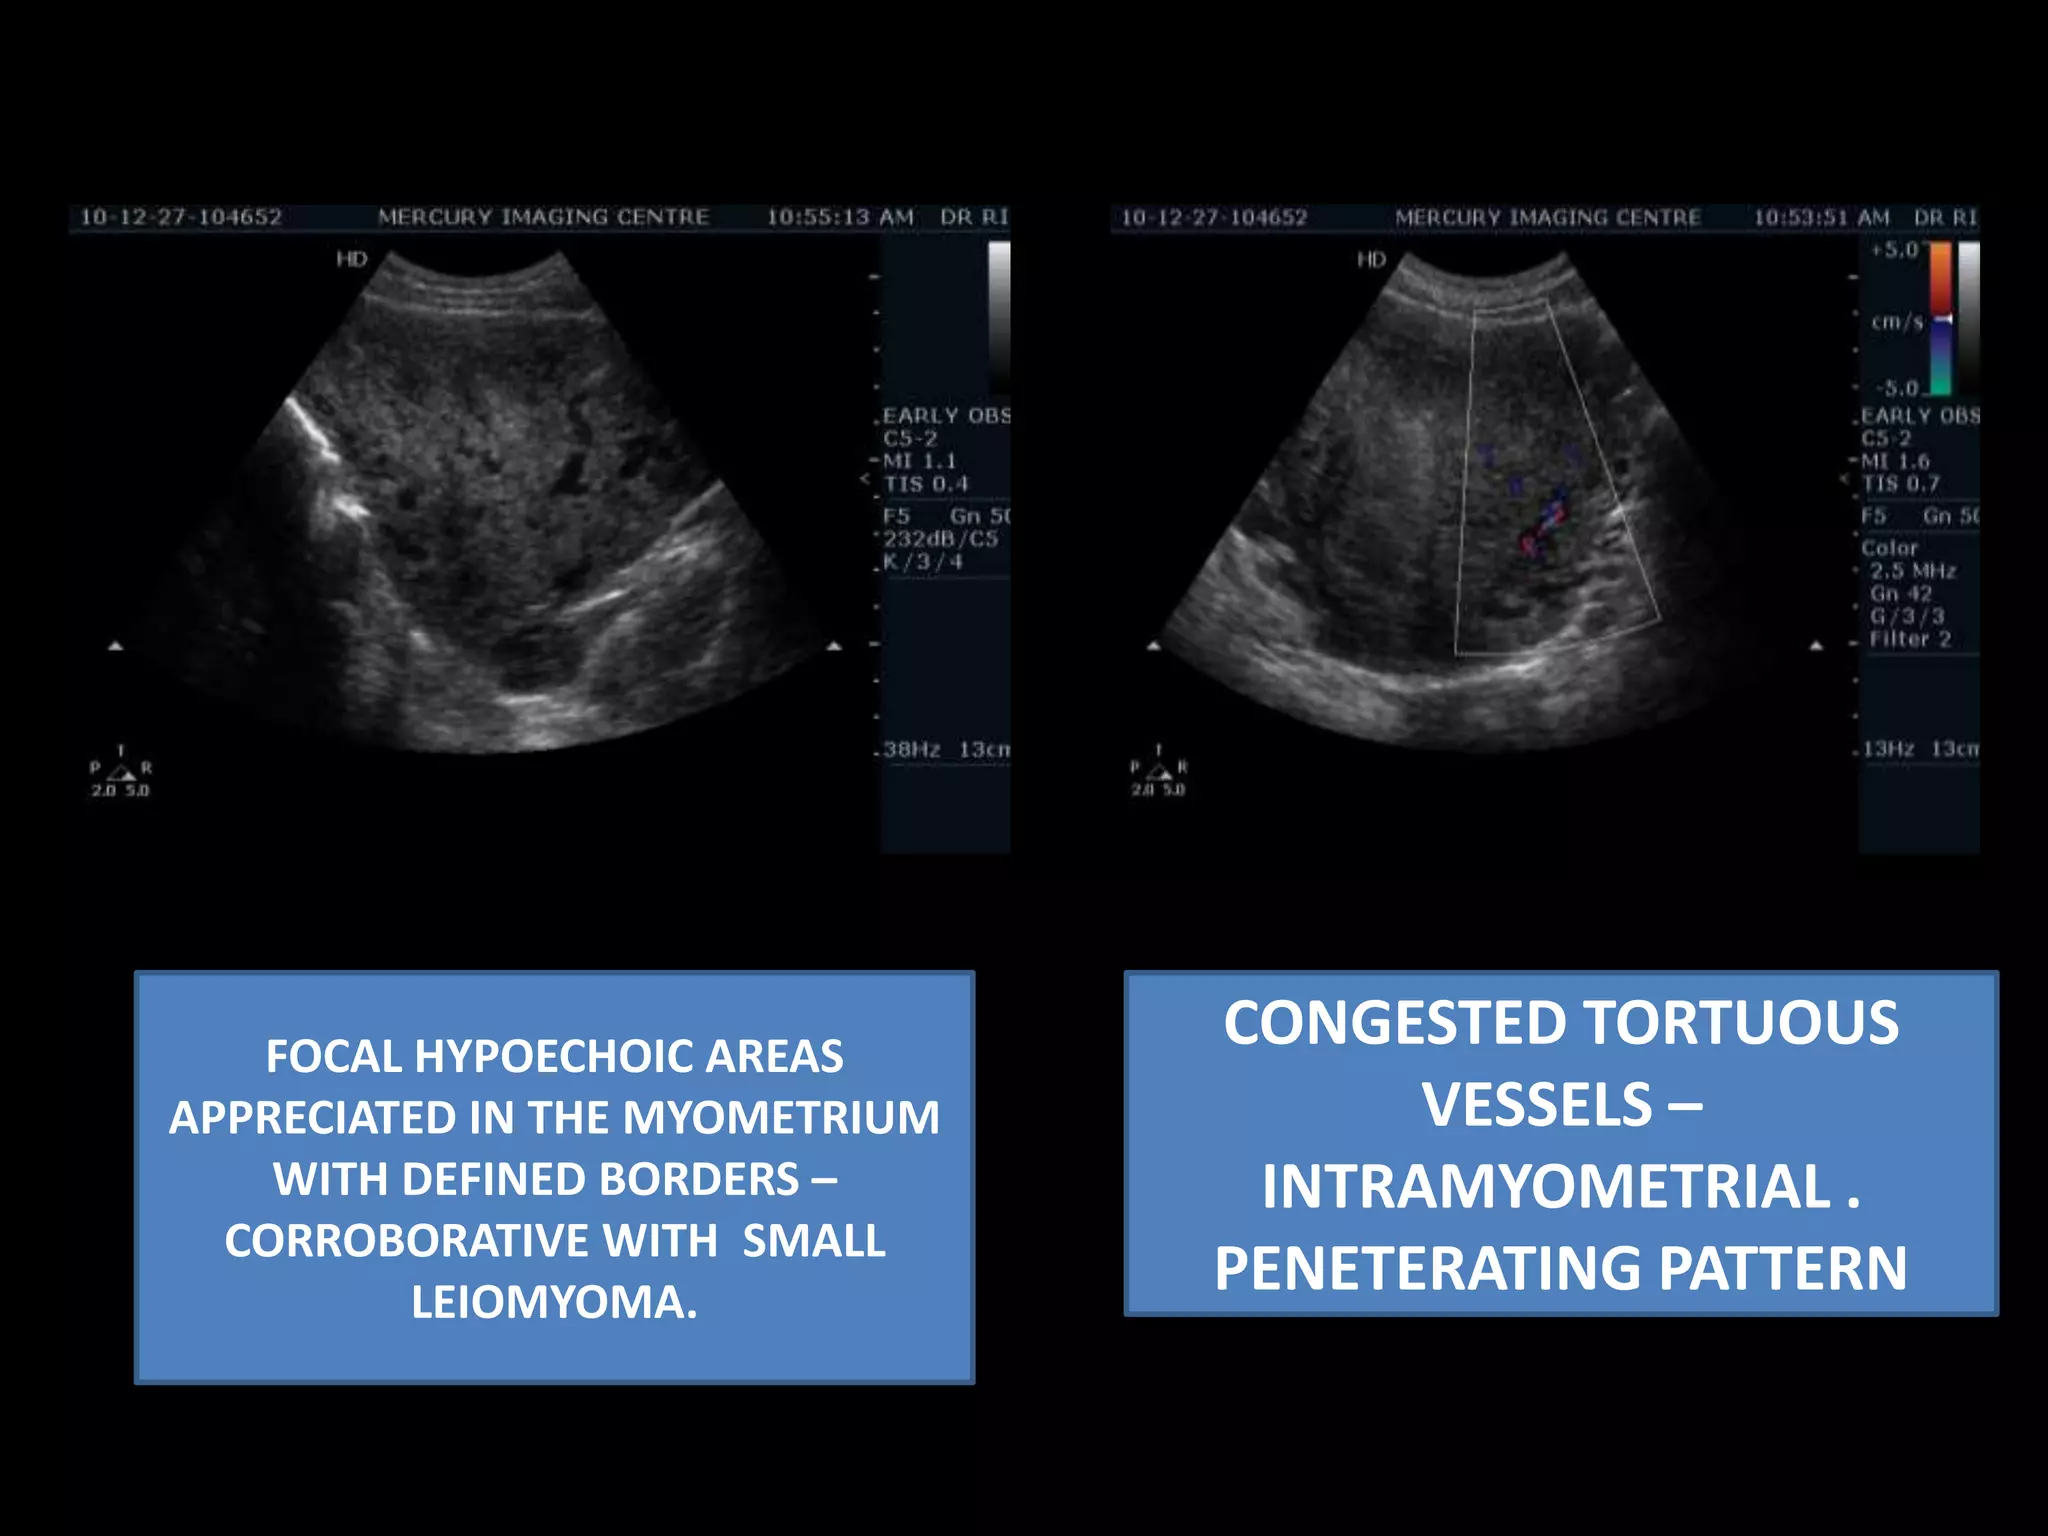

CONGESTED TORTUOUS VESSELS – INTRAMYOMETRIAL . PENETERATING PATTERNFOCAL HYPOECHOIC AREAS APPRECIATED IN THE MYOMETRIUM WITH DEFINED BORDERS – CORROBORATIVE WITH  SMALL LEIOMYOMA.

CONGESTED TORTUOUS VESSELS– INTRAMYOMETRIAL . PENETERATING PATTERNFOCAL HYPOECHOIC AREAS APPRECIATED IN THE MYOMETRIUM WITH DEFINED BORDERS – CORROBORATIVE WITH SMALL LEIOMYOMA.